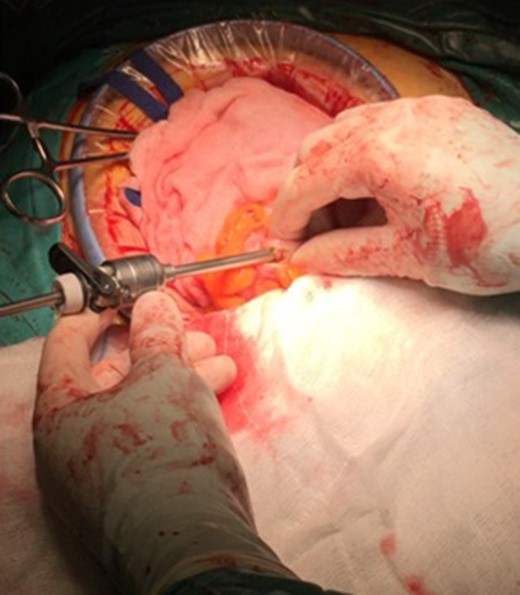

An isolation of the peritoneal cavity with compresses was initially performed. A cross-section of the peripheral truncation was performed on the colonic tape at the point where the ileocolonic anastomosis would be later created. A 10 mm laparoscopic port was inserted in the hole and CO2 insufflations started (Fig. 1). After bowel dilatation the camera was inserted through the laparoscopic port in the colon lumen. During the time the camera is intraluminal, water injection is provided, to avoid thermal injury of the mucosa. Overview of the lumen, until the splenic flexure bend and the beginning of the descending colon was performed. A hole was then applied to the colic tape at the lower third of the sigmoid (Fig. 2). Again, a 10 mm laparoscopic port was inserted and the laparoscopic camera was used to inspect the bowel lumen up to the splenic flexure. After the endoscopic inspection of the bowel has been completed, the laparoscopic ports were withdrawn (Fig. 3). The holes were converged with seromuscular stitches of the sigmoid and omentumplasty. A stapled side to side anastomosis was hen performed between terminal ileum and colon. The patient discharge hospital without any complication on the eighth postoperative day. The histopathology of the specimen shows low grade adenocarcinoma of the colon, pT4bN1b.

The insertion of the port at the sigmoid colon and the isolated operation field with compresses.